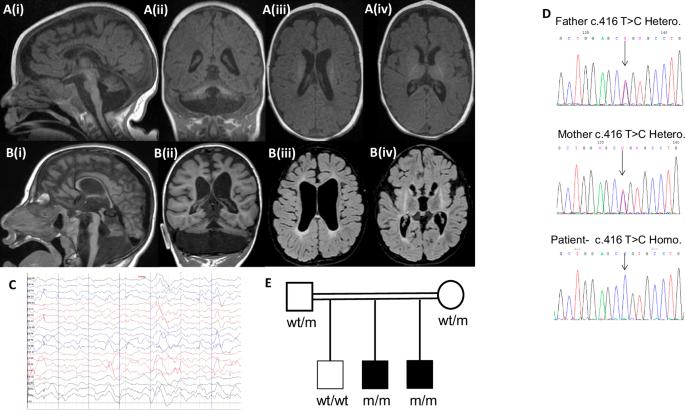

桥小脑发育不全(PCH)是一组以小脑和桥小脑发育不全、可变脑受累、小头畸形、严重的整体发育迟缓(GDD)和癫痫为特征的疾病。我们在两个兄弟姐妹中寻找PCH的遗传原因。通过全外显子组测序进行遗传检查,然后进行Sanger验证。用人类野生型基因拯救的morpholino敲低斑马鱼胚胎来评估小脑发育和运动功能。采用转染小鼠海马培养物和电穿孔小鼠胚胎来评估功能对神经元形态和发育的影响。两例患者均表现为重度GDD、严重小头畸形、白内障和不同程度的癫痫发作。mri显示明显的小脑和脑桥发育不全。两者都是C . 416t > C, p.(Leu139Pro) MED29变异的纯合子,预计该变异具有致病性。MED29 morpholino敲低斑马鱼的运动和小脑gaba能神经元的发育均受到损害,并被人类野生型基因表达拯救。在体外实验中,敲低小鼠海马神经元中MED29的shrna会减少神经突的长度和树突化,并在体内引起胚胎神经元迁移缺陷。med29p .(Leu139Pro)的过表达与功能丧失一致。综上所述,中介复合物调节转录过程,特定亚基的缺陷与涉及PCH的不同神经发育表型相关。我们认为MED29是PCH的一个新的危险基因。

Pontocerebellar hypoplasia (PCH) represents a group of disorders characterized by cerebellum and pons hypoplasia, variable cerebral involvement, microcephaly, severe global developmental delay (GDD), and seizures. We sought the genetic cause of PCH in two siblings. Genetic workup was performed by whole-exome sequencing followed by Sanger validation. Morpholino-knockdown zebrafish embryos with human wild-type gene rescue were used to assess cerebellar development and motor function. Transfected mouse hippocampal cultures and electroporated mouse embryos were employed to assess functional effects on neuronal morphology and development. Both patients presented with profound GDD, severe microcephaly, cataracts, and variably seizures. Their MRIs demonstrated marked cerebellar and pontine hypoplasia. Both were homozygous for a c.416T > C, p.(Leu139Pro) MED29 variant which was predicted to be pathogenic. Locomotion and cerebellar GABAergic neurons development were both impaired in MED29 Morpholino-knockdown zebrafish and rescued by human wild-type gene expression. ShRNA-knockdown of MED29 in mouse hippocampal neurons decreased neurite length and arborization in vitro, and caused defective embryonic neuronal migration in vivo. Overexpression of MED29 p.(Leu139Pro) was consistent with a loss-of-function. Taken together, the Mediator complex regulates transcription processes, and defects in particular subunits are associated with distinct neurodevelopmental phenotypes involving PCH. We conclude that MED29 is a novel risk gene for PCH.